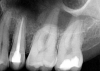

The patient returned for final evaluation of the provisional calcium-hydroxide endodontic therapy and resolution of the infection (33 days postoperatively). Fistula was not present; the tooth was not sensitive to percussion or mastication. The gold crown was removed using a high-speed metal cutting bur, the remaining caries were excavated conservatively, and the endodontic therapy was completed. Placement of glass-fiber reinforced composite and composite core buildup took place. The natural tooth structure to receive the glass-fiber post and a long-term restoration was available (Figure 8). Within one appointment, the tooth was restored (Figure 9). The patient was instructed to return for clinical and radiographic evaluation after 6 to 12 months to determine progression of periodontal healing. At that time, if the healing were adequate and the tooth were stable, evaluation of the tooth would be considered every 3 to 4 years.7

Fig 8. Gold crown removed, dentin excavated, canals shaped and filled.

Figure 8